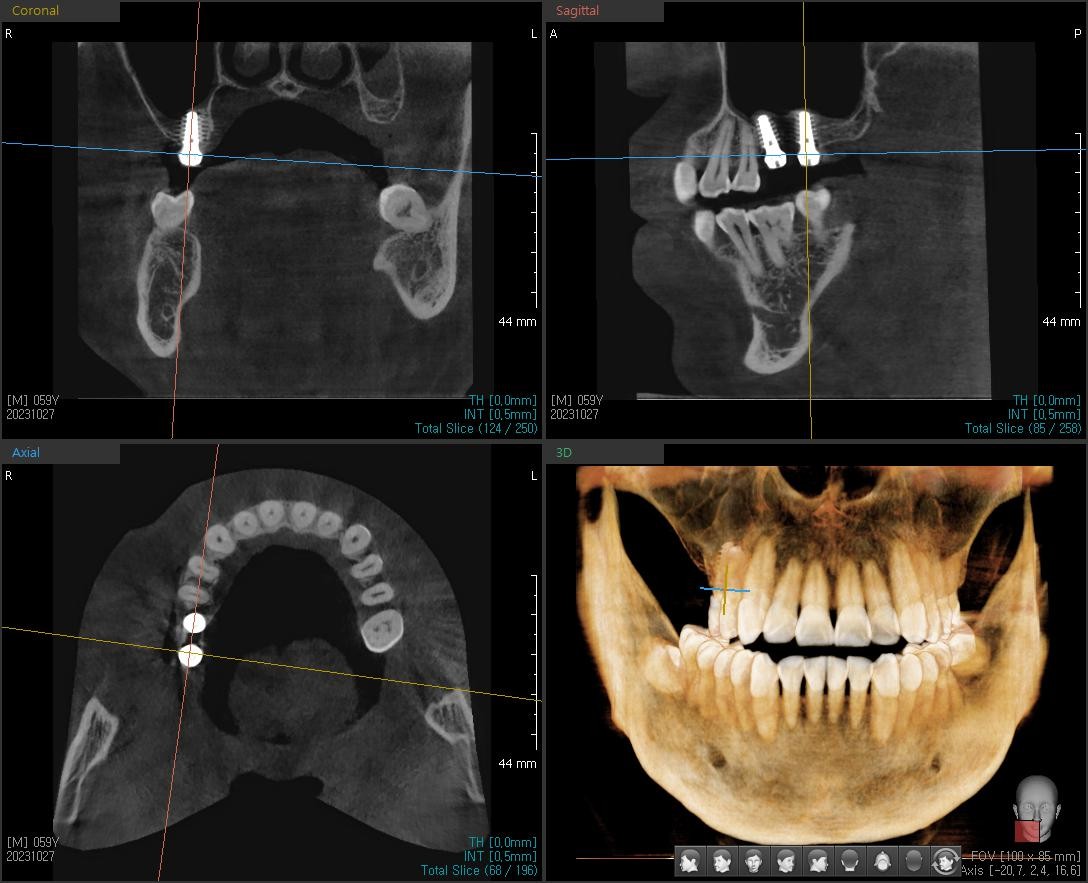

½Ä¸³ÈÄ ÆÄ³ë¶ó¸¶ »çÁøÀÔ´Ï´Ù.»ó¾Çµ¿ °Å»óÀ» ÁøÇà ÇßÀ¾´Ï´Ù.À̰͵µ ÀÕ¸ö Àý°³¸¦ ÇÏÁö ¾Ê°í »ó¾Çµ¿ ¸·À» °Å»óÇѰæ¿ìÀÔ´Ï´Ù.

ÀÌ°Ô ¹Ù·Î ¿äÁò ÀúÈñ º´¿ø¿¡¼ ¸¹ÀÌ ÇÏ´Â ÃÖ¼Ò Ä§½À ÀÓÇöõÆ®ÀÔ´Ï´Ù.

´ÙÀ½¿¡´Â ±¸°³» »çÁøÀ» ¿Ã·Á¤Áº¸µµ·Ï ÇÒ°Ô¿ä.